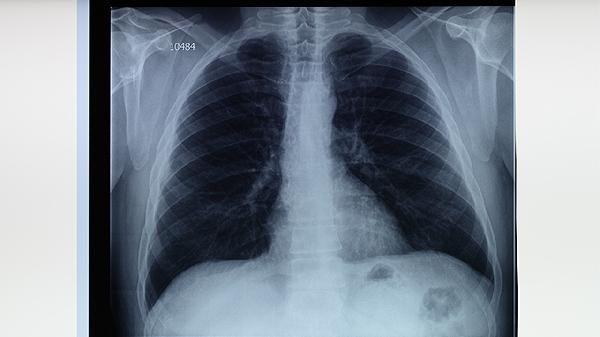

胸部X線檢查能發(fā)現(xiàn)肺結(jié)核引起的肺部病變特征,如上葉尖后段或下葉背段的浸潤(rùn)影、空洞形成等典型表現(xiàn)。該方法對(duì)早期粟粒性肺結(jié)核的敏感性較低,需結(jié)合其他檢查綜合判斷。孕婦等特殊人群需謹(jǐn)慎選擇,必要時(shí)可采用鉛防護(hù)措施。